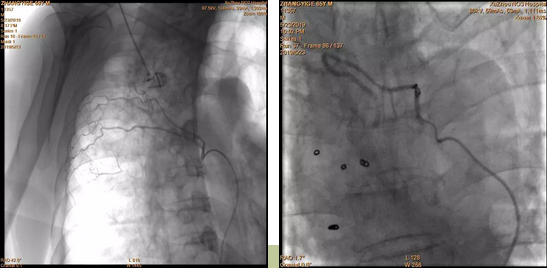

介入科李鵬飛醫生見到張大爺時(shí),他的情況已相當危險,鮮血不斷從他口鼻噴出來,人已經(jīng)昏迷不醒,而張大爺的血壓、血氧飽和度數值一度極低。分析患者的胸部CT 後(hòu),李鵬飛醫生判斷患者是支氣管擴張誘發(fā)的咯血,需要緊急進(jìn)行血管造影,查找出血點并進(jìn)行栓塞止血。通過(guò)造影發(fā)現,張大爺肺部果然有血管破裂。當即,李鵬飛醫生利用一根纖細的導管和栓塞材料徹底封堵了出血點,經(jīng)過(guò)造影複查,止血點封堵成(chéng)功,患者轉危爲安。

左圖:右側肋間動脈參與出血;

右圖:右支氣管動脈栓塞彈簧圈後(hòu)。